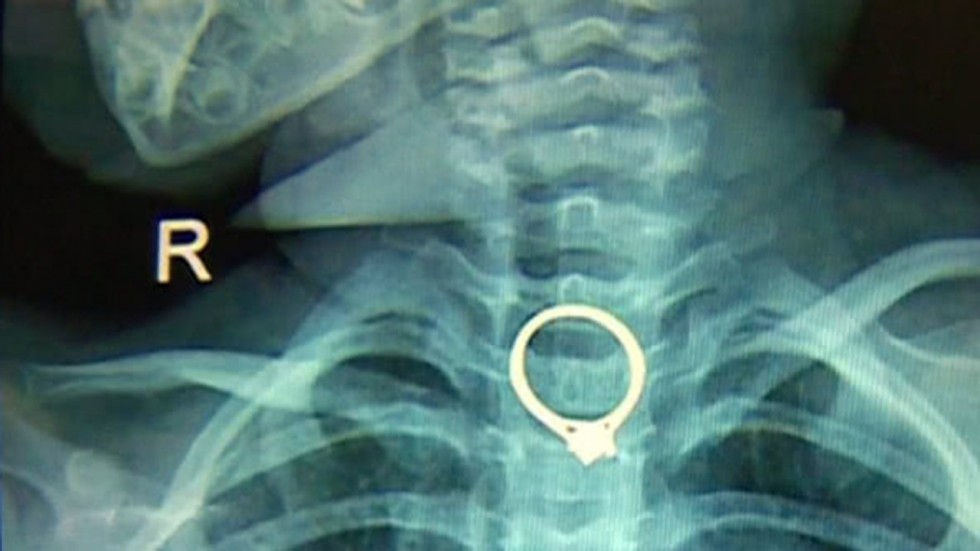

Chiếc nhẫn nằm tại thực quản của em bé. Ảnh: SCMP

Tại đây, các bác sĩ phát hiện chiếc nhẫn mắc kẹt trong thực quản của cô bé. Bác sĩ Chen Gang, người thực hiện ca phẫu thuật cho em bé nói: “Chiếc nhẫn có khá nhiều vết sắc. Nếu cô bé nuốt sâu hơn, chiếc nhẫn sẽ đi tới dạ dày và gây ra hậu quả nghiêm trọng”.